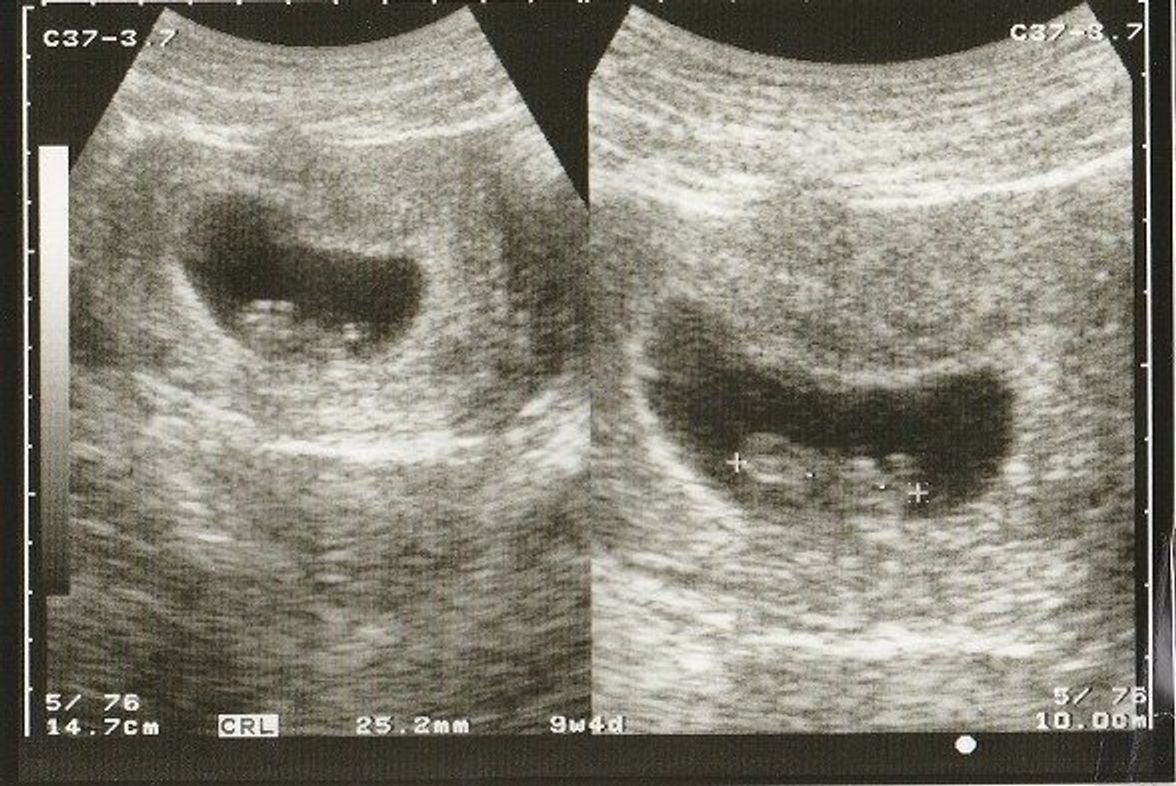

妊娠9週の赤ちゃんの大きさ(胎児頭殿長:CRL)は~30mm、胎嚢(GS)は57cm、体重は1~3g程度です。 ちょうどいちご1個分くらいの大きさです。 胎児はヒトらしい形に成長してきており、区切りができて頭と身体が分かれてきます。 顔や手足の指などの細かい部位も少しずつできてくる時期です。 また、生殖器の発達が始まるのも妊娠9週頃でしょう。 また 人間らしい形になる 妊娠9週の胎児は体の大きさも30mm程度に成長して体重も3g~12gくらいになります。 指も1本ずつ離れてきます。 心臓もほとんど完成して赤ちゃんの心拍音も力強く聞こえるようになるでしょう。 また首もまっすぐになって体は2頭身になり、これからはさらにバランスよく3頭身に変化していくことになるでしょう。 だんだんと赤ちゃんが